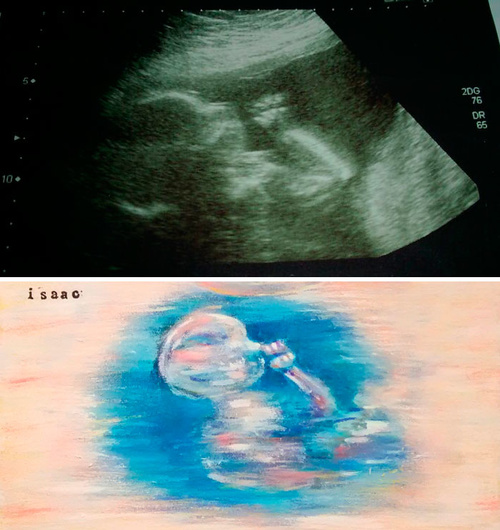

Ecografii în culori: Mama care transformă orice pântec în operă de artă

Mișcările bebelușului în burtă: când încep, cum le recunoști și când trebuie să suni la medic

Prima dată când simți că ceva se mișcă în burtă e un moment pe care nu îl uiți. Dar ce e normal, ce nu e și cum îți dai seama că totul e bine?